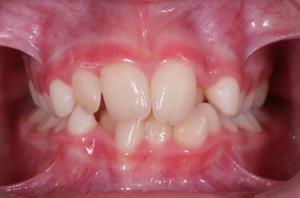

L’orthopédie dento-faciale, communément appelée « orthodontie », est la spécialité dentaire consacrée à l’étude et au traitement des troubles liés aux anomalies de la forme des mâchoires et de la position des dents.

L’orthodontie permet de corriger les malpositions dentaires ainsi que les anomalies de taille et de position des maxillaires afin de retrouver une denture fonctionnelle et esthétique.

Entre 8 et 11 ans environ, l’enfant est en denture mixte, c’est-à-dire qu’il présente à la fois des dents de lait et des dents définitives.

Chez l’adolescent, le traitement concerne les dents définitives et a pour but d’aligner les dents, de corriger les décalages dentaires et squelettiques et d‘obtenir un bon emboîtement des dents entre elles.

Les objectifs sont à la fois esthétiques (harmonisation du sourire et de la face) et fonctionnels (obtention d’une bonne occlusion, d’un équilibre squelettique et normalisation des fonctions orofaciales de respiration, déglutition, phonation et mastication).